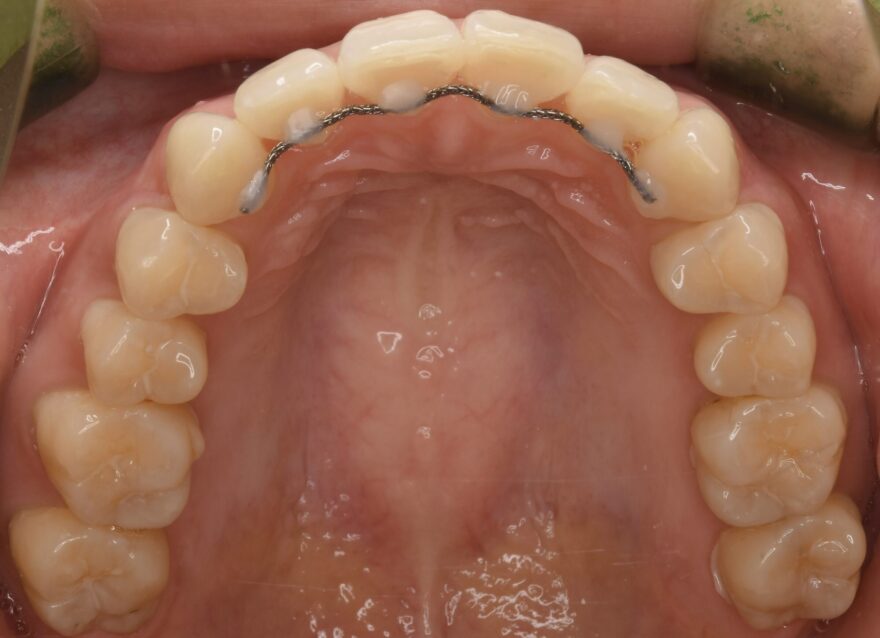

治療中の口腔内写真

上顎は裏側に矯正装置が付いています。

口蓋に2本の歯科矯正用アンカースクリューが埋め込まれ、裏側の矯正装置とゴムで繋がっていることがわかります。

上顎の前歯にはワイヤーによる保定装置を装着しました。